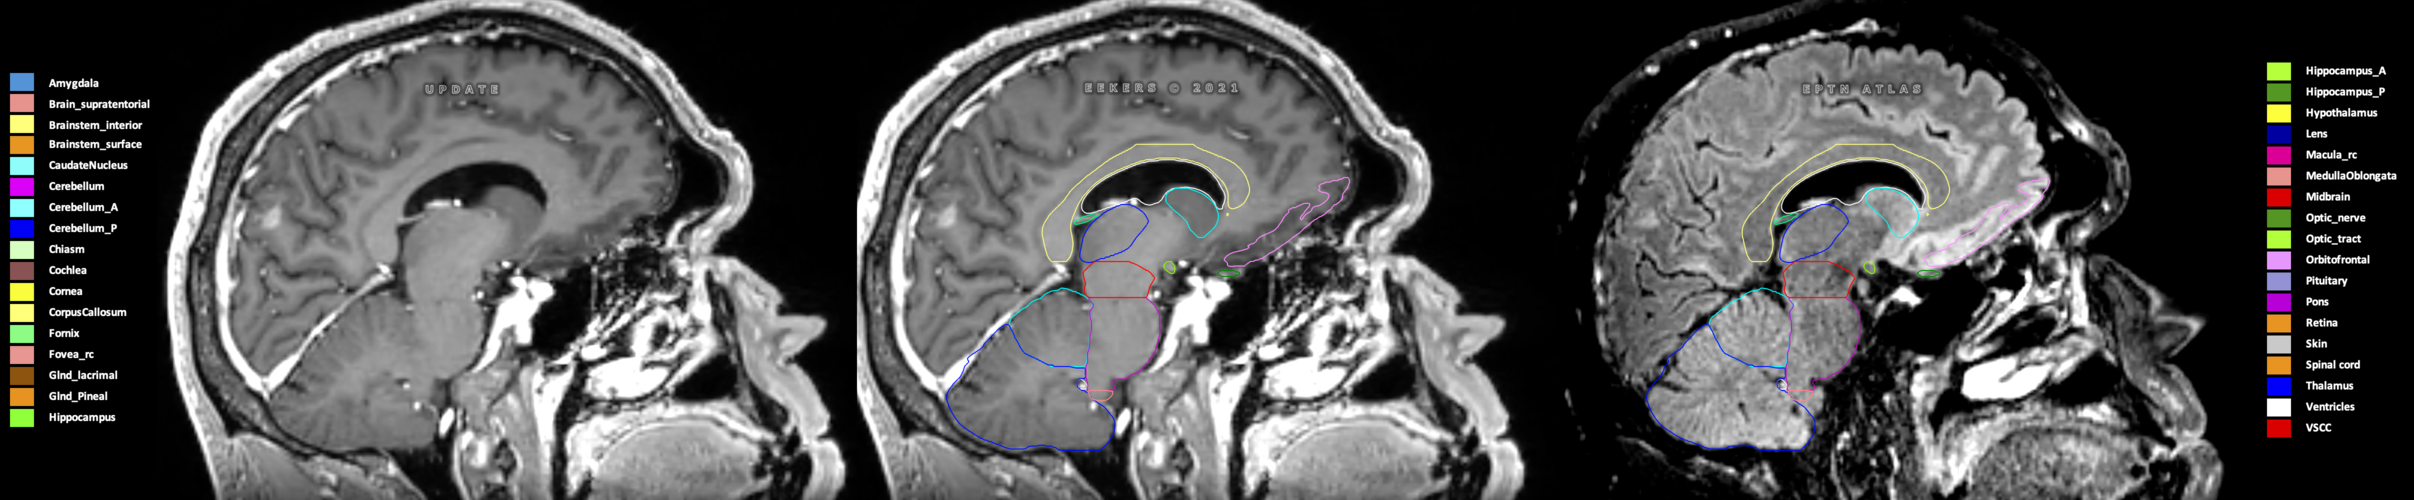

Eekers et al. have published an international neurological atlas for contouring of organs at risk in consensus with the European Particle Therapy Network (EPTN) in 2018 and an update in 2021. The purpose of this consensus atlas is to decrease inter- and intra-observer variability in delineating OARs relevant for neuro-oncology.

Included are all OARs known to be relevant for radiation-induced toxicity in neuro-oncology: brain, brainstem (midbrain, pons, medulla oblongata), chiasm, cerebellum (anterior & posterior), cochlea, cornea, hippocampus (anterior & posterior), hypothalamus, lens, lacrimal gland, optic nerve, pituitary, skin, and vestibular & semicircular canals. To further facilitate research on cognition, vision and radiological changes after irradiation of the brain, potential clinically-relevant OARs are included: amygdala, caudate nucleus, cerebellum (anterior & posterior), corpus callosum, fornix, macula, optic tract, orbitofrontal cortex, periventricular space (PVS), pineal gland, and thalamus.

Three-dimensional delineation of the 25 consensus OARs for neuro-oncology are shown on CT (WW/WL 120/40, 3000/600), 3T MR images, (T1Gd, T2FLAIR 1mm) and 7T MR (MP2RAGE 0.7 mm). All are presented in transversal, sagittal and coronal view.